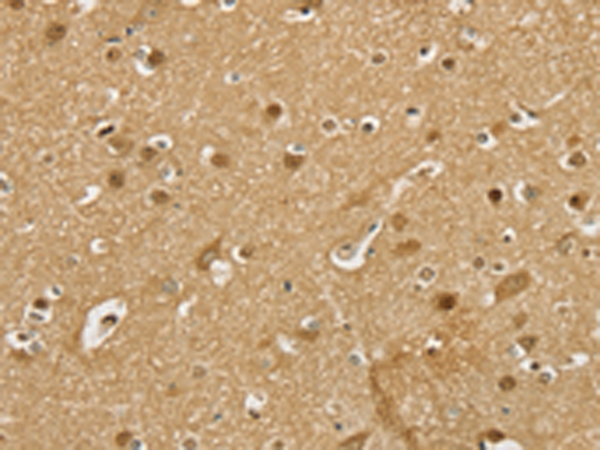

分类: 科研抗体货号: P08637别名: CYPA; CYPH; HEL-S-69p应用: WB,IHC反应种属: Human, Mouse, Rat